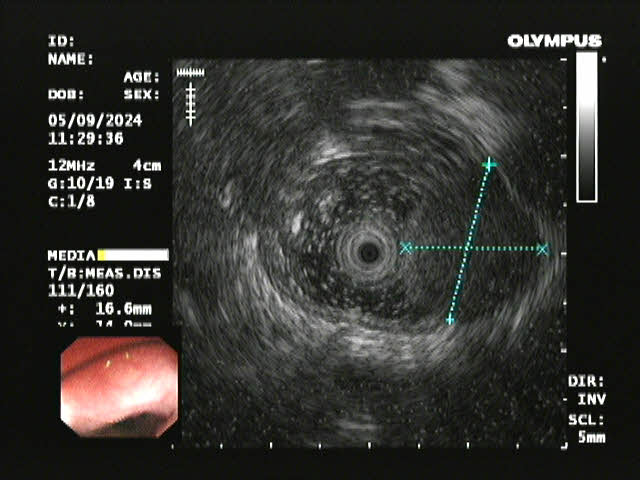

超声内镜

患者李某因胸骨后异物感20余天入院,在外院进行胃镜检查提示食管距门齿约26cm处见黏膜下肿瘤,在樱花动漫 超声胃镜提示该肿瘤呈低回声,局限于黏膜下层,固有肌层完整;胸部CT提示该肿瘤直径>2cm,位于食管中下段,增强扫描轻度强化,前与左主支气管相邻,后紧贴胸主动脉,手术过程中稍有不慎就可能发生大出血,危及患者生命,手术难度和风险可想而知。